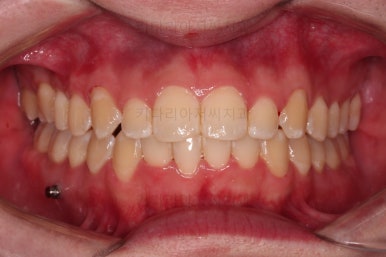

이제 전후 비교를 해볼게요.

1년 7개월 만에 매우 고난이도의 치료를 임플란트 없이 사랑니까지 당겨와서 사용한 만족스러운 치료였습니다.

우측의 결손치아보다 뒤쪽에 있는 치아는 크기나 모양이 원래의 큰 어금니보다 작고 다르게 생겨서 100% 이상적인 교합을 얻기는 한계가 있었어요.

하지만 임플란트 없이 충분히 가능할 수 있게끔 해주어서 환자분도 매우 만족하는 치료가 되었어요.

뿌리도 남아있었고 골 결손도 심했던터라 뒤쪽 치아들이 잘 움직일 것을 고지해 드렸었지만 다행히 거의 문제 없이 치아가 잘 움직였고요.

대신 해당 치아는 뼈가 약하다는 걸 환자분도 인지하시고 관리를 잘해야되는 부분입니다.